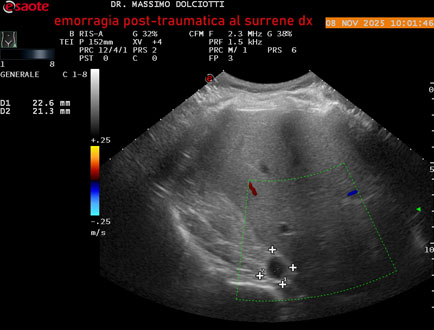

Data inserimento: 10/11/2025

Ecografia del: 08/11/2025

Strumento: Esaote MyLab Eight

Sonda: Convex Multifrequenza 1-8 MHz

Età Paziente: M 49 anni

Motivazione dell'esame: follow up per emorragia al surrene destro post-traumatica (incidente stradale).

Commento all'esame: le immagini ed il video documentano in sede surrenalica destra, formazione ipo-anecogena, a margini definiti, ovalare, delle dimensioni di 38,6 x 19,7 mm, da ricondurre ad emorragia post-traumatica.

Conclusioni: emorragia post-traumatica al surrene destro (post-traumatic hemorrhage to the right adrenal gland).

Presentazione: Dr. Massimo Dolciotti - Ancona

Elaborazione digitale: Andrea Dini - Ancona